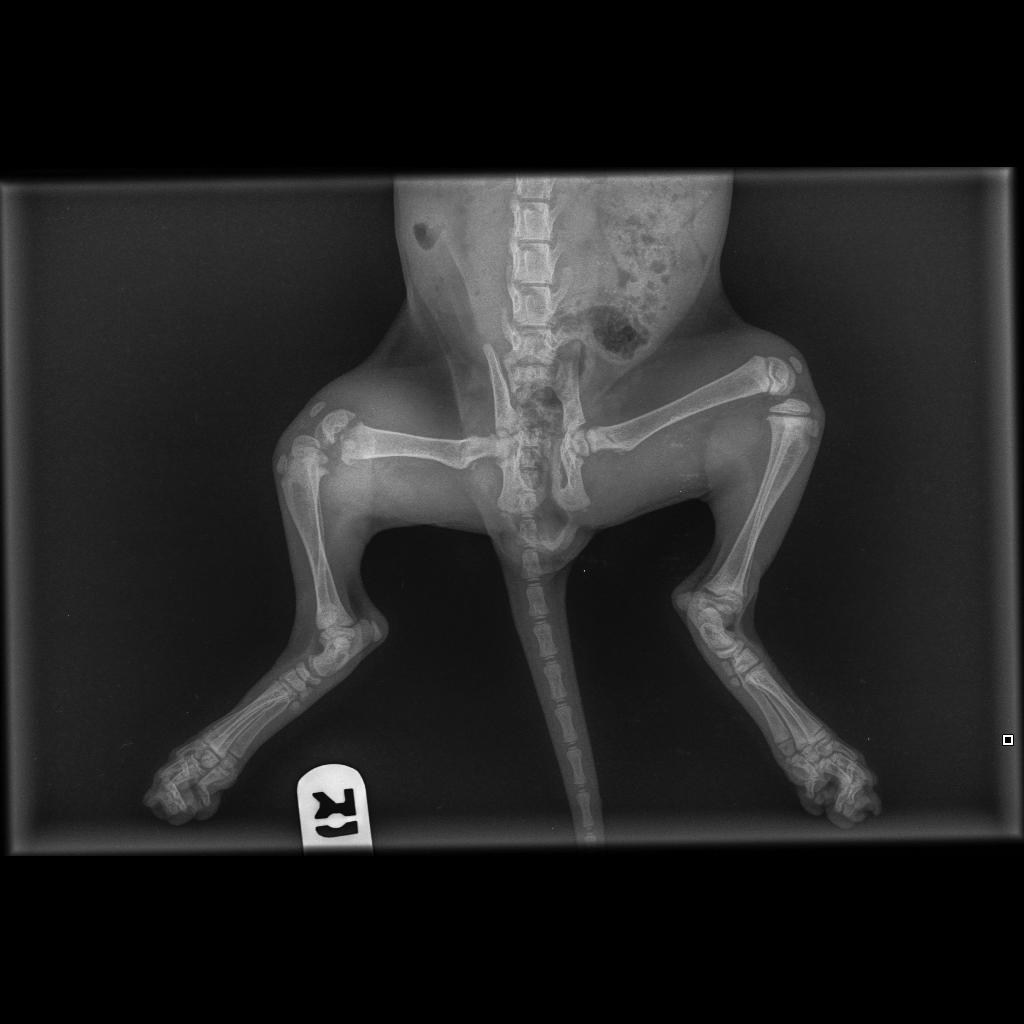

S: NWB right hind, very inflamed and slightly dangling right stifle Clinically well otherwise CVS nad Temp 38 Lnn normal Had a lot of flea dirt when found but much healthier now eating well Has been having meloxicam the last day or two- seems happier 2 x radiopgraphs taken VD and ML view of right hind findings: complete femural growth plate fracture, type 1 salter harris fracture.

Plan: Chat to a surgeon or orthoped to find out best way forward repair vs amputation? Until then bandaged with a splint Meloxicam 0.1ml SID PO Rest Drugs Dispensed.